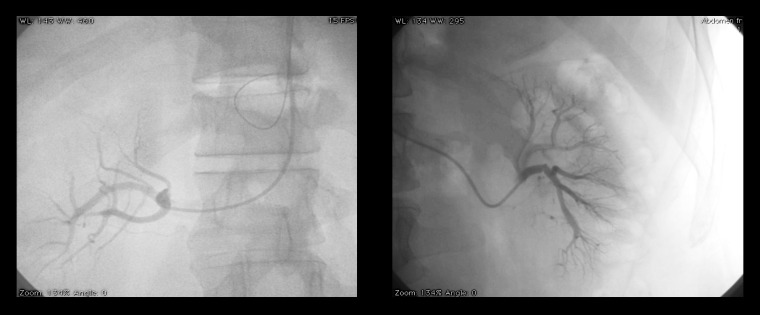

腹主动脉瘤在多种解剖情况下都会对治疗构成挑战,从而使血管内治疗变得更加复杂。肾下段腹主动脉瘤(JR-AAA)的定义是没有近端着床区,因此必须使用各种技术来获得足够的颈部以固定内支架,同时不引起肾动脉和内脏分支的闭塞。平行移植物技术、医生改良支架移植物、工业定制的内膜假体和现成的分支内膜假体是用于近端颈部不足的腹部动脉瘤的技术,但每种技术都有其适应症、局限性和风险。在这一治疗难题中,我们介绍了一例使用平行移植物技术对 JR-AAA 进行紧急血管内治疗的病例,取得了良好的中期效果,并讨论了治疗方案。

Abdominal aortic aneurysms can constitute a therapeutic challenge in several anatomical scenarios, making endovascular treatment more complex. A juxtarenal abdominal aortic aneurysm (JR-AAA) is defined by the absence of a proximal landing zone in the infrarenal segment and, therefore, techniques must be used to obtain an adequate neck for fixing the endoprostheses without provoking occlusion of renal arteries and visceral branches. The parallel grafts technique, physician-modified stent-graft, industry customized endoprostheses, and off-the-shelf branched endoprosthesis are techniques used in abdominal aneurysms with inadequate proximal neck, but each technique has its indications, limitations, and risks. In this therapeutic challenge, we present a case of urgent endovascular treatment of a JR-AAA using a parallel grafts technique, with good medium-term results, and discuss the therapeutic options.